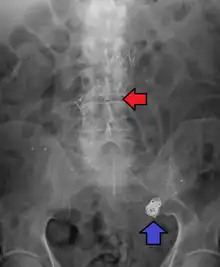

Endovascular stent and endovascular coil